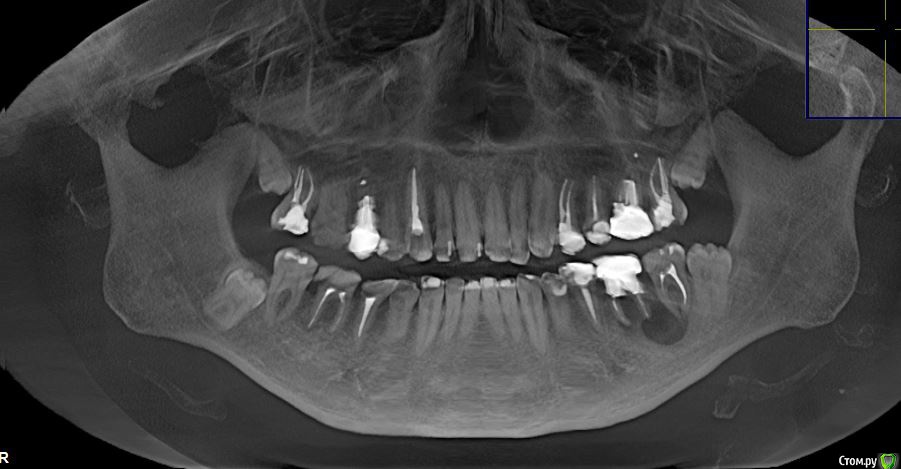

Anna275 Опубликовано 18 октября, 2018 Поделиться Опубликовано 18 октября, 2018 Здравствуйте! Несколько дней назад мужу диагностировали на КТ радикулярную кисту в нижней челюсти слева. Врач учреждения, где делали КТ, расписал следующий план лечения: удаление трех зубов (6-ка, 7-ка, 8-ка), цистоэктомия, костная пластика челюстно-лицевой области (замещение костного дефекта или заполнение биоактивным материалом), применение препарата PRF (2 пробирки). Ну и в дальнейшем установка имплантов. Мы пока пребываем в шоке, уже три дня читаю интернет, записались на пару консультаций в разные клиники, но пока время не подошло; параллельно решила попросить совета на этом сайте. Уважаемые стоматологи, вы согласны с тем, что требуется удаление аж трех зубов??? Консервативное лечение в нашем случае уже никак? Для информации - в 6-ке стоит штифт.Прошу прощение за техническую неподкованность, прикрепляю копии снимков, если нужно (и можно на этом сайте - могу выложить результаты КТ в формате iso). Заранее спасибо! Ссылка на комментарий

DmitrySH Опубликовано 18 октября, 2018 Поделиться Опубликовано 18 октября, 2018 Шестой - 100% удаление из за сильного разрушенияВосьмой - удаляется из-за своей не функциональности Седьмой - сам по себе не так плох, можно и попытаться сохранить, только это усложнит и растянет всю работу Удаление трех сразу и имплантация -более прогнозируемо Ссылка на комментарий

red_butler Опубликовано 19 октября, 2018 Поделиться Опубликовано 19 октября, 2018 Перелечить седьмой. Убрать шестой (без вариантов) на сколько получится вычистить оболочку кисты через лунку. Через пару тройку месяцев принимать решение о цистэктомии. Восьмой убрать до протезирования седьмого.P.s. на верхней челюсти два кандидата на удаление 1 Ссылка на комментарий

kriokov Опубликовано 19 октября, 2018 Поделиться Опубликовано 19 октября, 2018 1 этап удалил бы три зуба , 6, 7, 8, с одномоментной цистэктомией (удаление кисты) через лунки удаленных зубов, никакие бы костные заменители для восстановления дефекта на первом этапе не применял.(дефект маленький , наружная кортикальная везде почти целая, заживет сам)2. через 6 месяцев повторно клкт этой зоны, с целью решения вопроса о возможности установки имплантатов и необходимости "костной пластики" 1 Ссылка на комментарий

Bier Опубликовано 20 октября, 2018 Поделиться Опубликовано 20 октября, 2018 Если хочется максимально спасать зубы, то 7й можно перелечить. 6й однозначно удаляется.в 8м смысла нет. Ссылка на комментарий